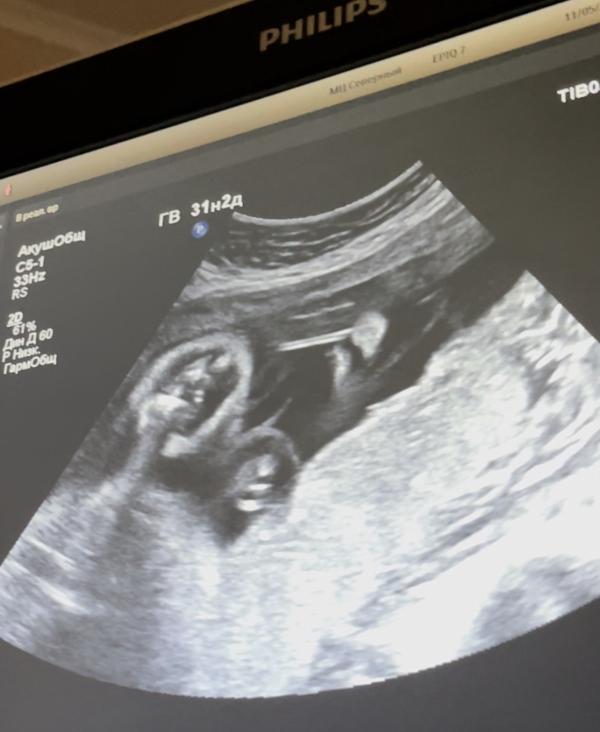

Сегодня была на узи. 31,2 вес 1560 гр. (девочка)

но по узи срок 30 недель. Так было и предыдущие 2 узи.